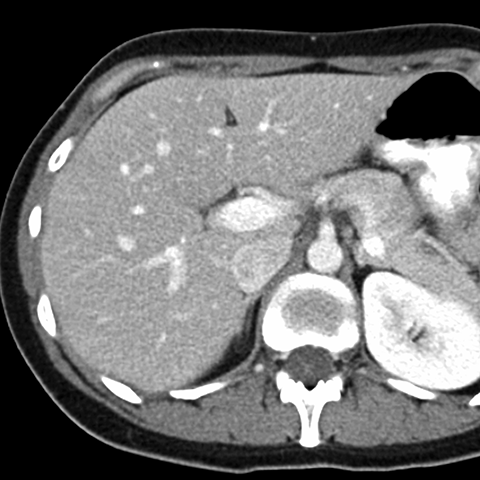

Normal Liver, CT ( axial ) [5 of 9]